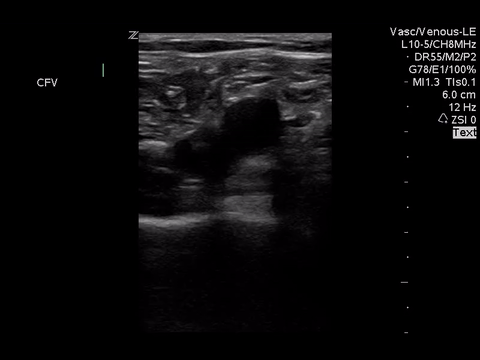

We can eliminate a few diagnoses off the differential with this scan. However, with the diagnosis of PE remaining a 2-point DVT scan was carried out:

Right lower extremity

|

In each of these images it appears the vein fully collapses with compression. We can conclude that there is likely no DVT present within the limitations of the 2-point compression scan (see discussion for further details)